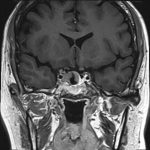

No.’25_82 手術前1

No.’25_82 手術前2